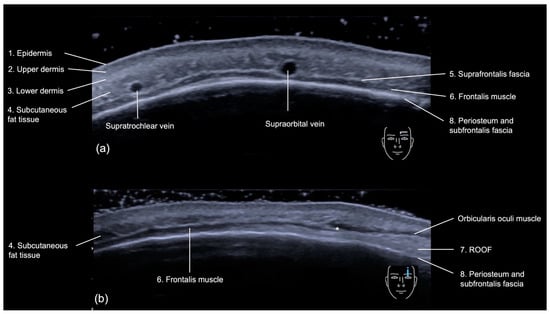

3.2.1. Sonographic Anatomy

- Epidermis: a hyperechoic line.

- Upper dermis: a hypoechoic homogeneous layer.

- Lower dermis: a hyperechoic layer.

- Subcutaneous fat tissue: a hypoechoic layer composed of fat lobules and hyperechoic septae.

- Suprafrontalis fascia: a thin hyperechoic upper layer of galea aponeurotica.

- Frontalis muscle: a hypoechoic band-like structure.

- Retro-Orbicularis Oculi Fat compartment (ROOF): a hyperechoic fibrous fat layer that separates the frontalis muscle from the bone. It can be appreciated in the inferolateral part of the forehead.

- Periosteum and subfrontalis fascia: a hyperechoic line showing combined imaging of these structures, with acoustic shadowing below. Due to the convexity and reflective nature of the frontal bone, there is usually a mirror imaging artefact.